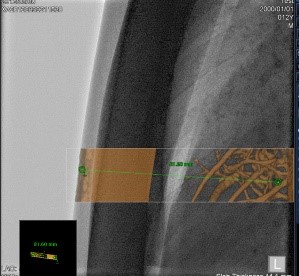

Програмне забезпечення для планування ендоваскулярного стентування аорти (EVAR)